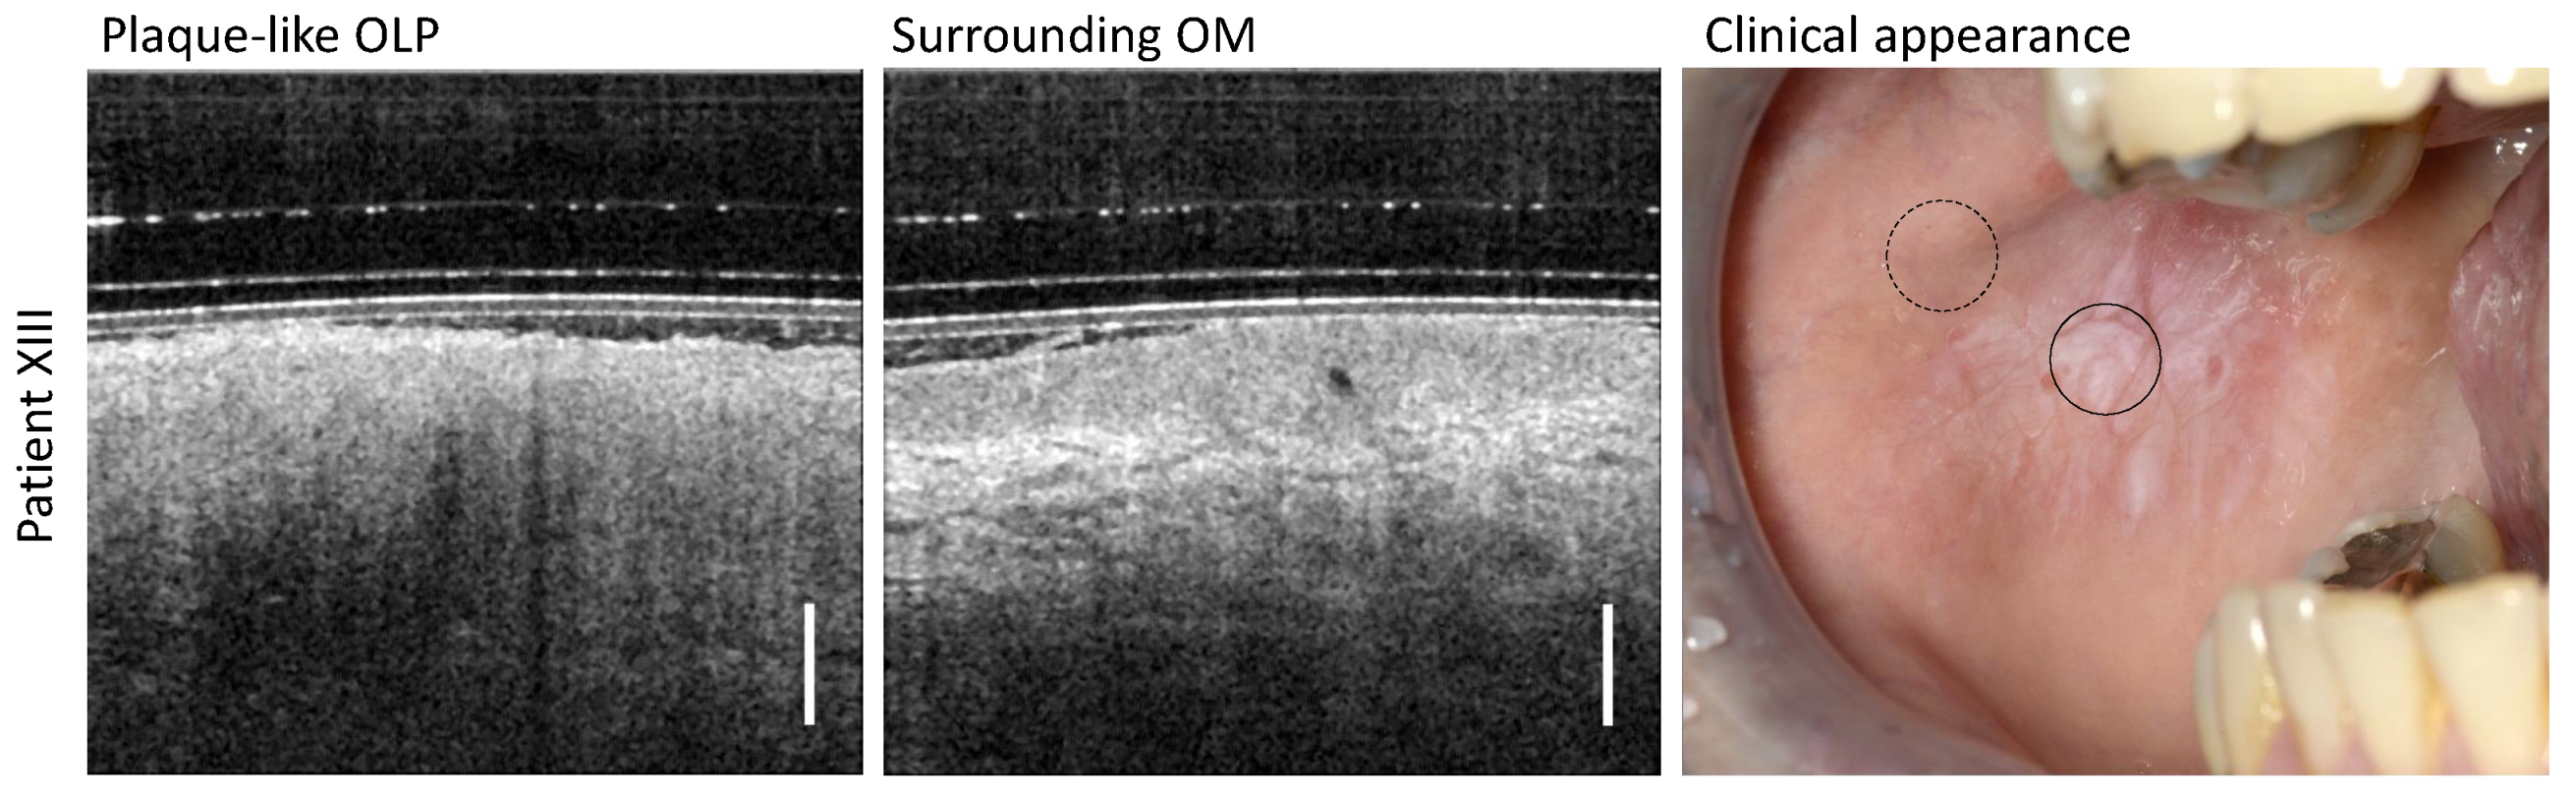

3.5. Plaque-like OLP

| Plaque-like OLP | hyperreflective layer at EP | |

| hyperkeratinization | no BM visibility | |

| large whitish homogenous OM | no layer differentiation | |

| no vessel network identification | ||

| XIII | female | 48 | OLP: right buccal mucosa; operation of the right arm | Propolis; clove oil; Ceterizin (anti-histamine agent) |